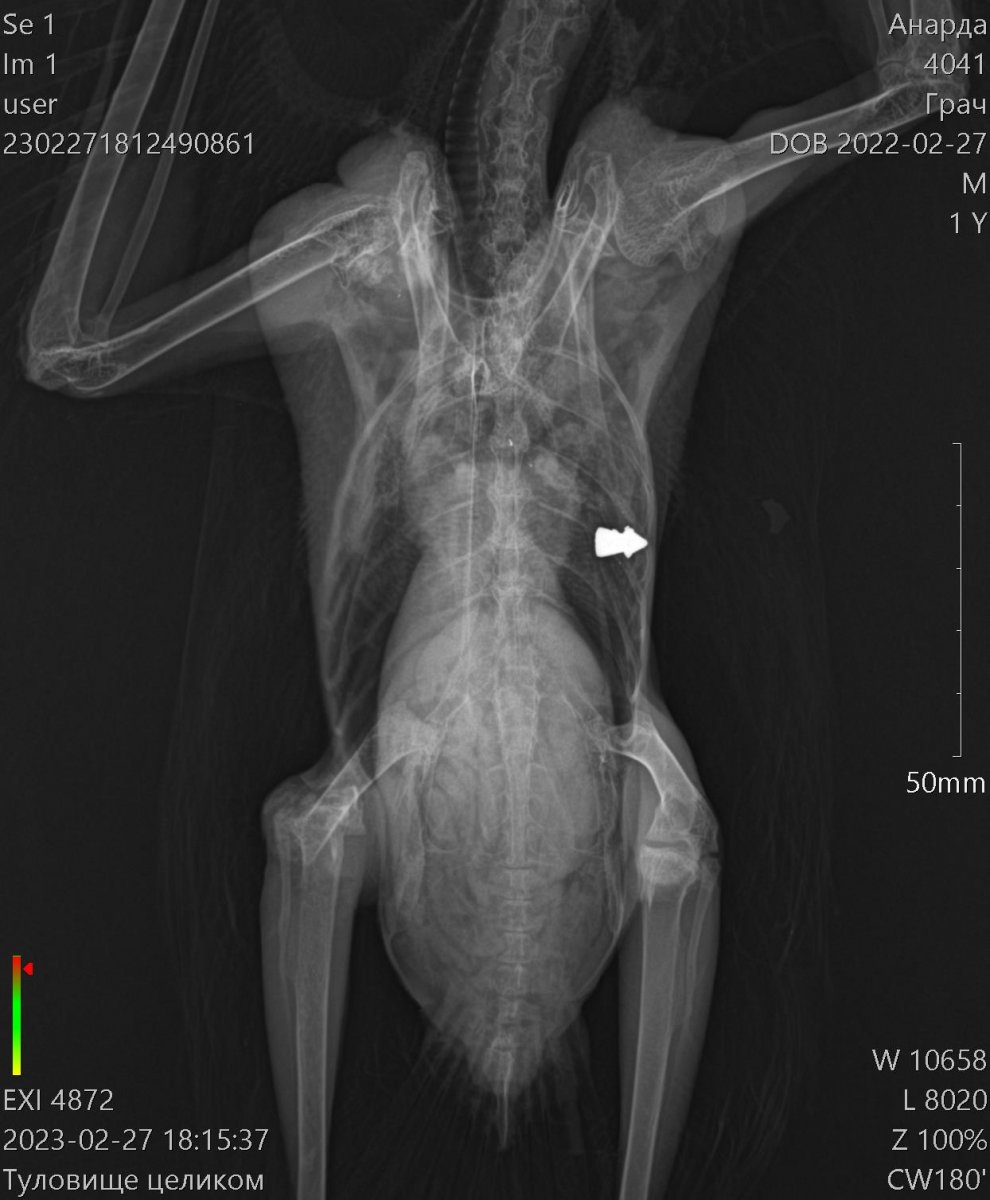

Доброго времени суток! Прошу строго меня не судить,так как оказался заложником ситуации ведь в отношении таких птиц не имел опыта совсем. Напишу вкратце. Шёл вечером домой,вижу лежит грач живой,ну я не смог пройти мимо и забрал его с собой.Повез к ветеринару,тот его пощупал и сказал что он травмирован и ничем помочь не может, сказал пусть поживёт у тебя месяц два, отойдёт и если все хорошо оклимется и улетит... Через месяц ничего не произошло, грач как хромал так и хромает, взлететь пытался но не смог. За это время я ему сделал вольер большой 2 метра в высоту и 5 в длину, научился правильно кормить. В общем понял что нарвался я на горе ветеринара и повёз в дорогую клинику, где сделали качественные снимки, оказалось его подстрелили, снимки прикреплю в тему. Сделали анализы, прописали лекарства, от паразитов, клещей итд. Но самое неприятное это то, что сказали что он летать не будет и ему нужна операция, каких у нас в Пятигорске нельзя осуществить. Подскажите пожалуйста, как нам быть? Кто сможет помочь нам? У нас в крае травили грызунов, средством которое запретили 35 лет назад, в итоге весь наш город и край усыпан трупами грачей, прямо везде даже в центре города,а своего я вроде думал что спас, но как оказалось нет :(